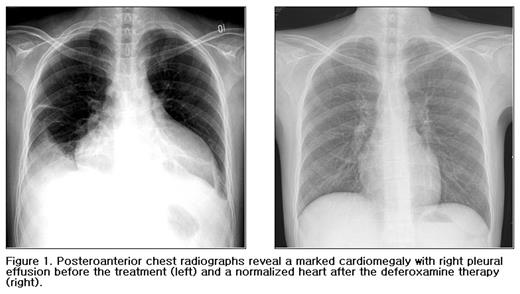

Posteroanterior chest radiographs reveal a marked cardiomegaly with right pleural effusion before the treatment (left) and a normalized heart after the deferoxamine therapy (right).

A 24-year-old male patient with hemochromatosis due to multiple packed red blood cell transfusions, was referred to our emergeny center for a treatment of severe aplastic anemia and dyspnea. He was diagnosed with aplastic anemia at the age of 11 and had developed a transfusional hemochromatosis after 5 years of multiple blood transfusions. He had dilated cardiomyopathy with ejection fraction of 4 % requiring diuretics and digitalis, multiple endocrine dysfunctions (hypothyroidism, hypoparathyroidism with hypocalcemia, cataract, and intracranial calcifications, diabetes, and gonadal dysfunction), liver dysfunction, generalized bleeding, and skin pigmentation (Fig.1-left). A total volume of packed red blood cell transfusion before deferoxamine therapy was about 96,000 ml and the number of transfused units of platelet concentrates were innumerable. He had received regular iron chelation therapy (continous intravenous infusion of deferoxamine, 50 mg/kg/day for 5 days q 3–4 weeks) for 7 years after multiple organ failures. His cytopenias and organ dysfunctions (heart, liver and skin) began to recover progressively in 2002, after four years of deferoxamine therapy. He had had complete normal ranges of his peripheral blood cell counts, heart size, and liver function two years ago (Fig.1-right & Fig.2). He has not received any transfusions for the last four years. This finding suggests that continuous deferoxamine infusion may play a role in immune regulation in addition to iron chelation effect.